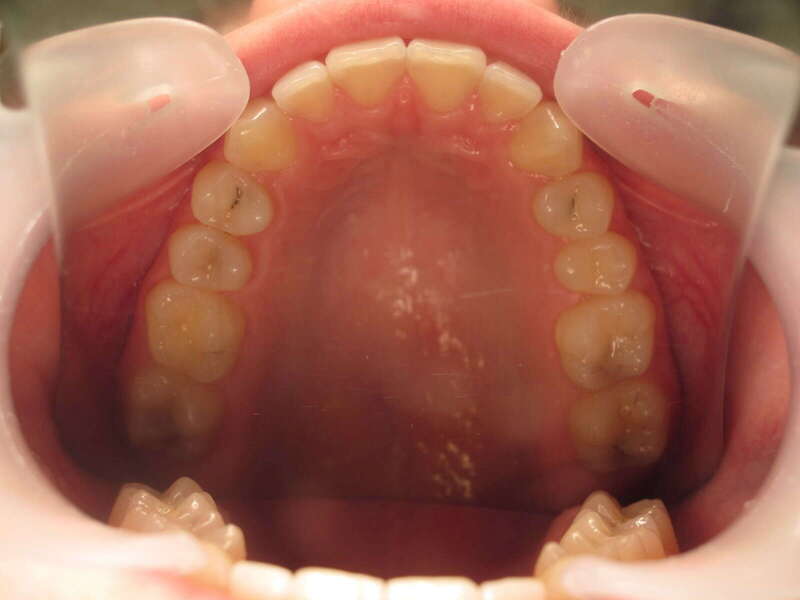

Cas n°1 traité par aligneurs - adolescent

Ce cas d’une adolescente illustre la correction d'une Classe II avec supraclusion par aligneurs. La stratégie thérapeutique a reposé sur une distalisation séquentielle de l'arcade supérieure. Ce mouvement précis a permis de reculer les dents maxillaires étape par étape pour annuler le surplomb (overjet) sans extractions.

• Correction fonctionnelle : Retour à un engrènement de Classe I stable et correction du recouvrement vertical.

• Esthétique restaurée : Harmonisation globale du sourire et du profil.

• Approche moderne : Un traitement discret, confortable et hautement prévisible.

Le résultat final montre une occlusion saine et un sourire parfaitement aligné, garantissant une santé dentaire et articulaire optimale pour l'avenir.